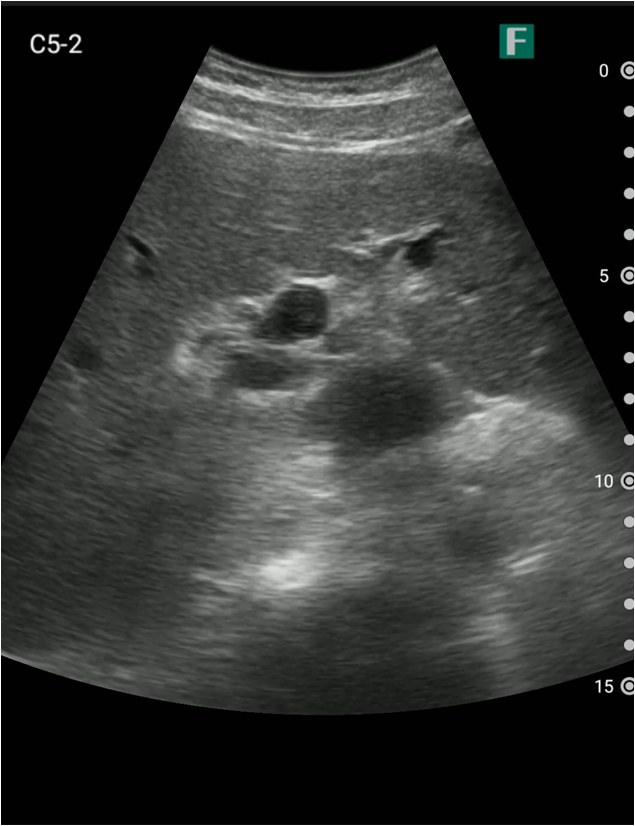

もう一つは入院患者様に対しての具体的な使用事例を紹介します。朝の回診の際にiViz airを使用し、例えば腹水のある患者様を診た際は、「今日は水の量が少なく、そこまでお腹は張ってないですね」、「今日はここに水が溜まっているんですけど、昨日より少ないですよ」など、日々の状態を患者様ご本人に伝えるようにしています。スマホで実際の画像も簡単にお見せできるので、患者様に実際に見ていただくことで少しでも不安を和らげてもらえるように心がけています。

そうして積極的に話をすると、不安そうな表情をする患者様はあまりいらっしゃらない印象を受けています。iViz airがあると患者様と会話をするきっかけにもなるため、コミュニケーションツールとしても実用的だと感じた事例でした。